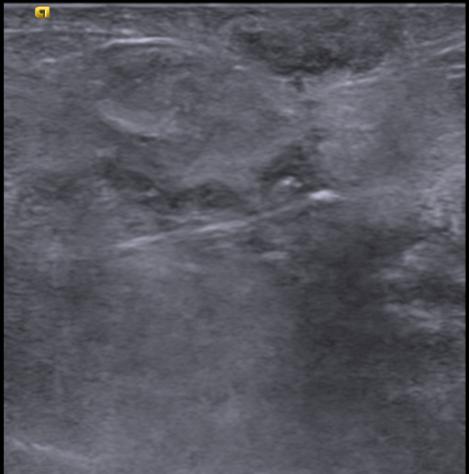

Left breast USG showing mass forming area consisting of multiple thickened dilated ducts extending into the subcutaneous region (straight white arrow). There is parenchymal edema surrounding this area of abnormality.

With a differential diagnosis of granulomatous mastitis and Invasive ductal carcinoma ,USG guided core Biopsy was done from the lesion

• Final Histopathology Chronic granulomatous mastitis.

• Gene X pert was positive for tuberculosis.

• Patient was started with ATT.